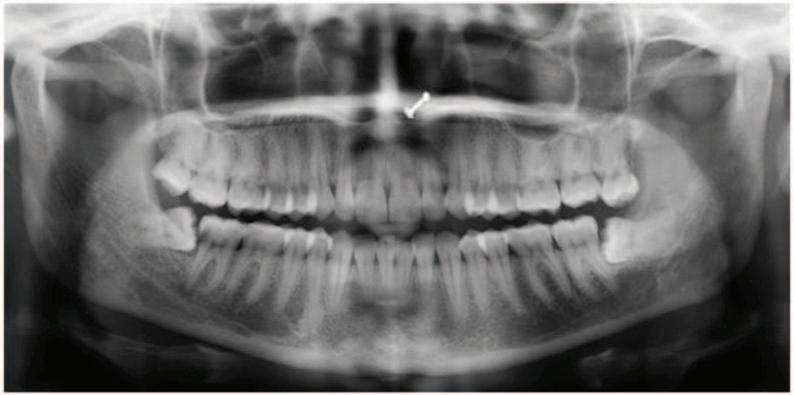

A 40-year-old female presents with a sharp pain on eating and drinking, especially cold drinks, which lasts for a few seconds. Her sleep is not disturbed. On clinical examination there were probable caries in the mandibular left second molar tooth, with no tenderness to percussion or palpation. A bitewing radiograph (Figure 1) was taken. The soft caries were removed and a carious pulp exposure occurred.

FIGURE 1: Bitewing radiograph.

1. Based on the classification of caries described by Bjørndal (2018), how would you describe the caries seen in the radiograph?